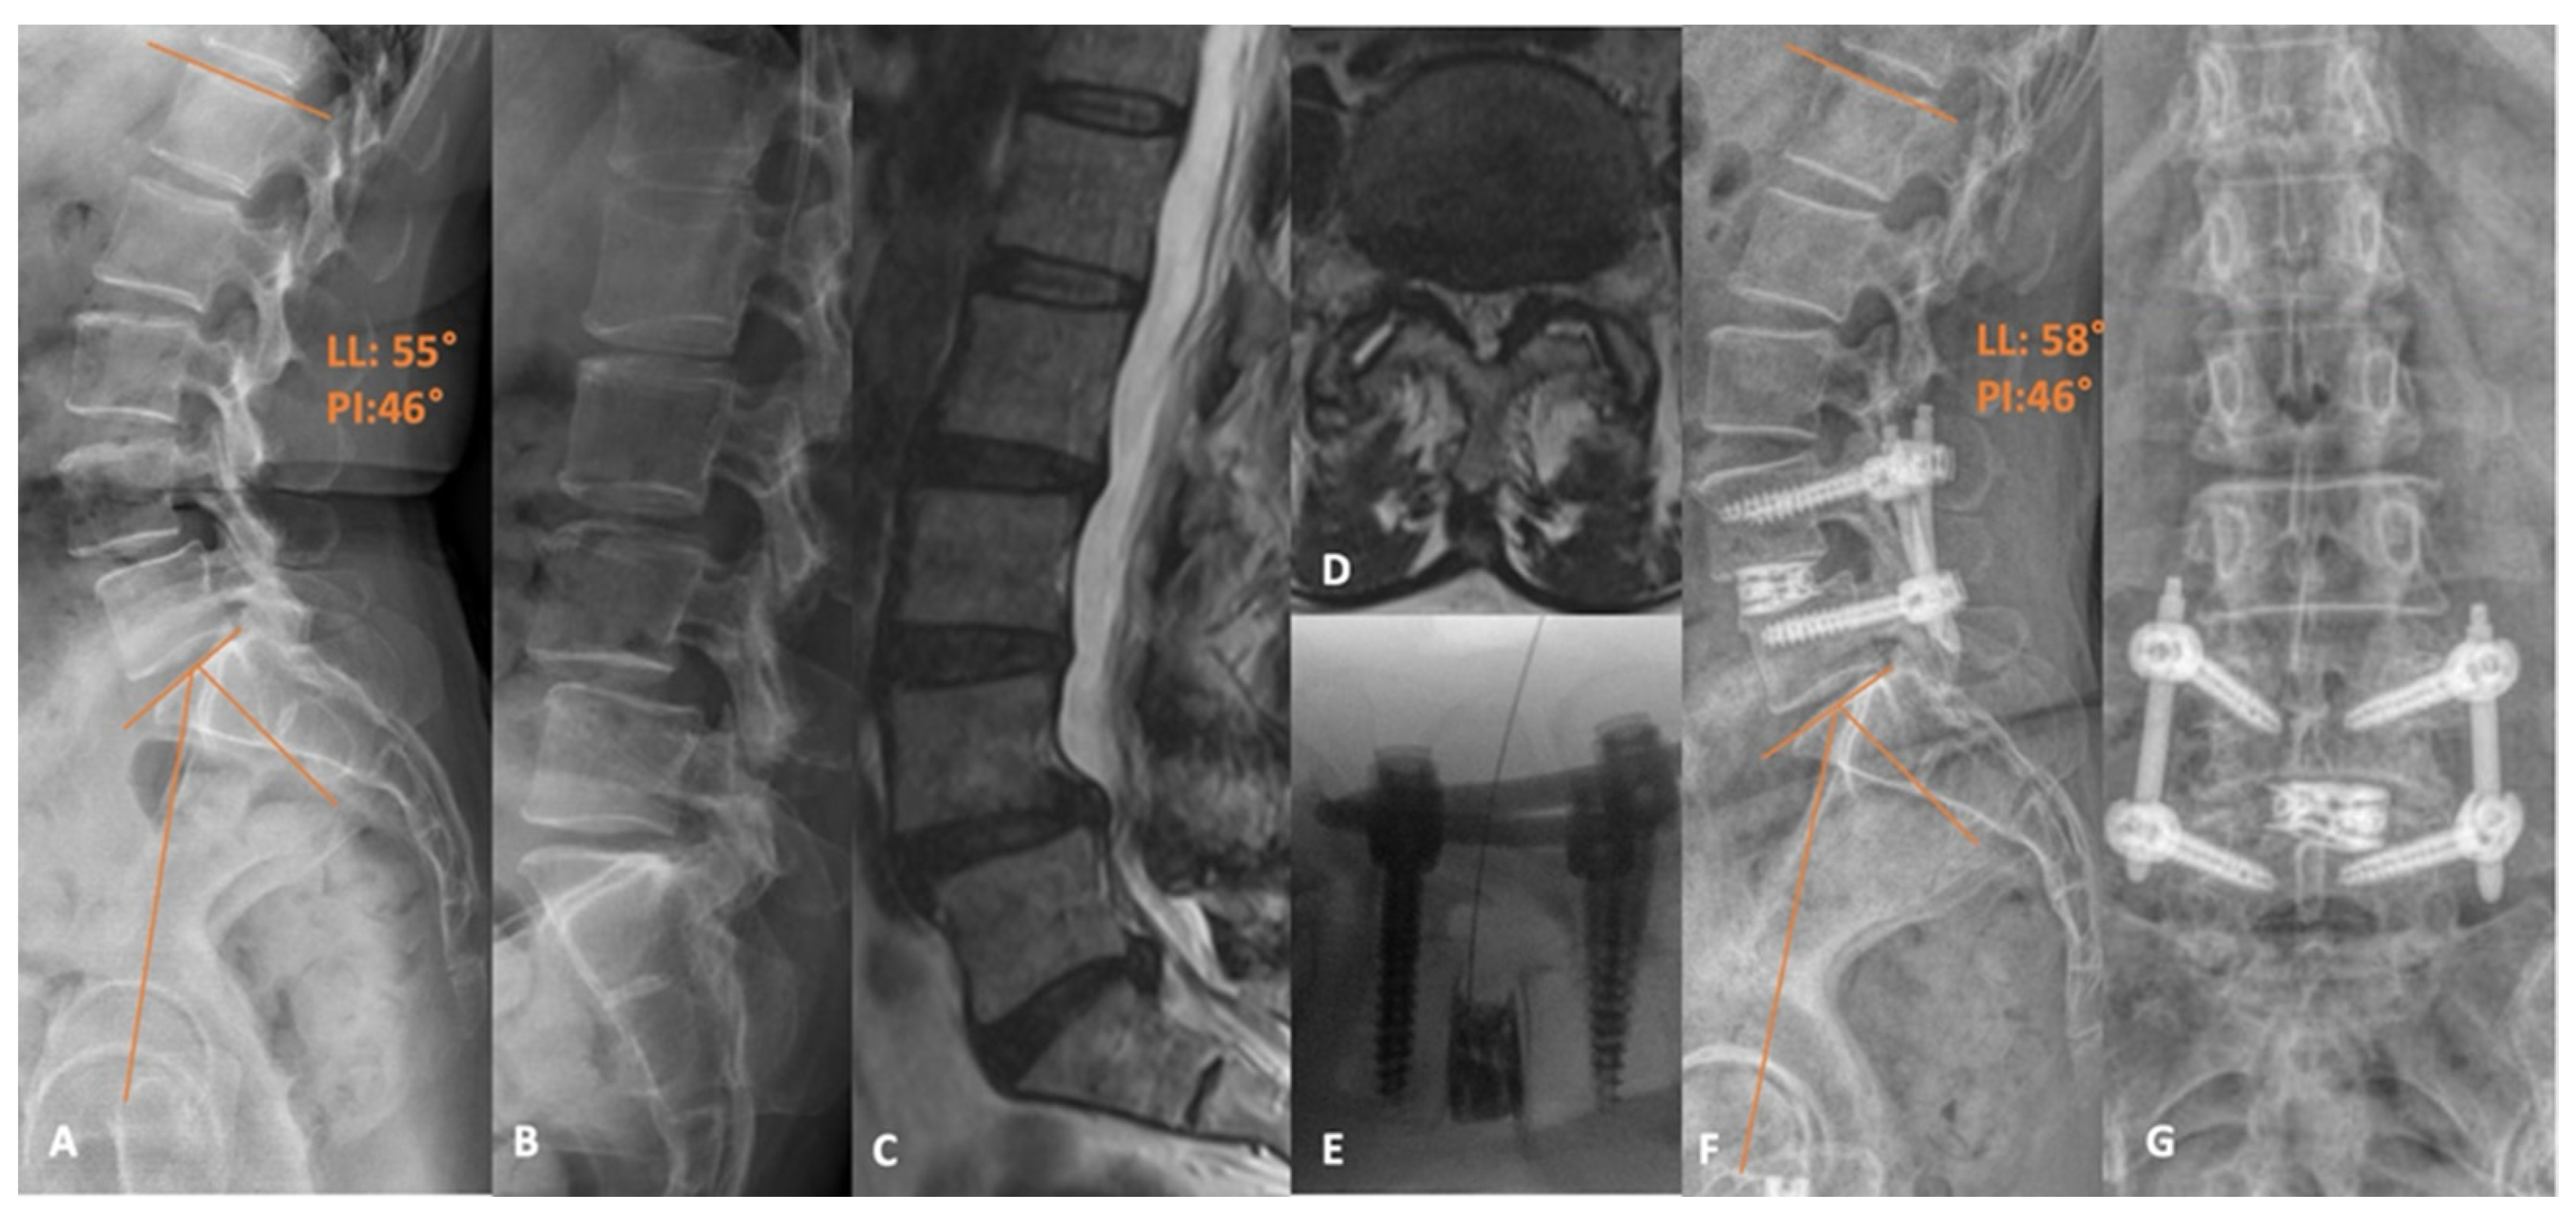

- Tabarestani, T.Q.; Sykes, D.A.W.; Maquoit, G.; Wang, T.Y.; Ayoub, C.M.; Shaffrey, C.I.; Wiggins, W.F.; Abd-El-Barr, M.M. Novel Merging of CT and MRI to Allow for Safe Navigation into Kambin’s Triangle for Percutaneous Lumbar Interbody Fusion-Initial Case Series Investigating Safety and Efficacy. Oper. Neurosurg. 2023, 24, 331–340. [Google Scholar] [CrossRef] [PubMed]